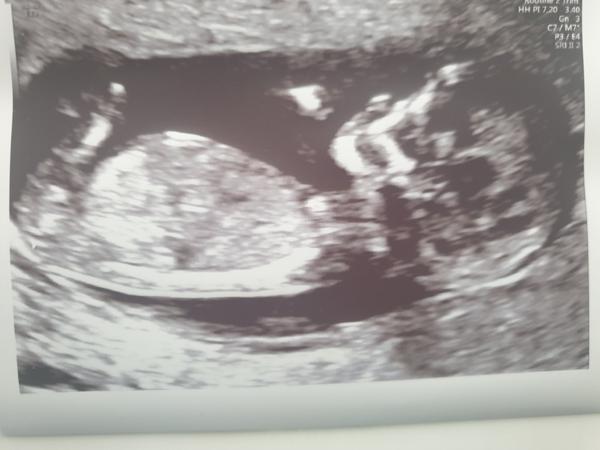

Ahoj holky, jsem spis tichý pozorovatel, jelikož k Vám už zas tak nepatřím 🙈 termín dle transferu 31.7, dle UTZ 2.8 … ALE dnes se musím podělit o radost 🙂 našla jsem srdíčko s angelsounds!!! Jsem tedy 10+6, ale myslím, ze je to nezaměnitelné - jako když jede vlak 🙂

Dnes bych měla být 11+4, mám dnes v 18.45 konečně další kontrolu, tak jsem nervózní. A ještě k tomu jdu k nové doktorce, jelikož můj gynekolog mě jen psychicky stresoval a ta péče byla teda skoro nulová. Tak jsem zvědavá.

Příští týden 17.1. mám 1. Screening. Tak snad vše dopadne dobře.